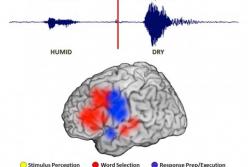

Ученые показали, как мысли движутся в мозге (видео)

Ученые показали, как мысли движутся в мозге (видео)

Движение мыслей в мозгеНейробиологи из США смогли отследить путь мыслей. Для того, чтобы провести эксперимент, специалисты привлекли 16 добровольцев с эпилепсией, передает FaceNews.